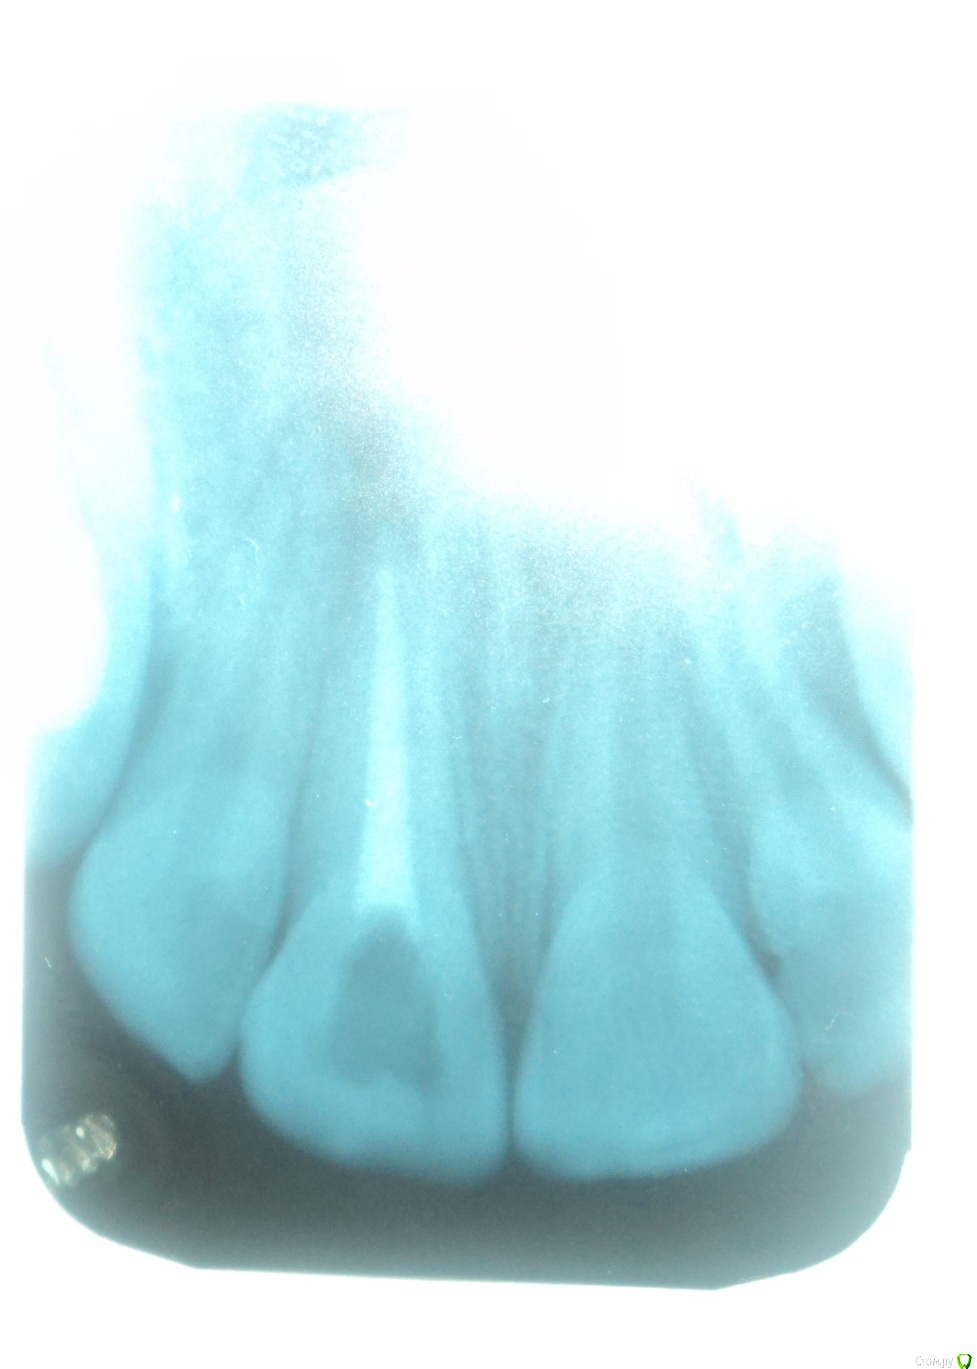

Здравствуйте! Примерно 12 лет назад у меня была травма переднего зуба после чего удалили нерв и  ввели в канал мне сказали метапекс, но по записям вроде не метапекс(фото с записями из карточки и снимки зуба прилагаю)  и запломбировали.  В течении примерно 10 лет (с 22.06.2005) этот зуб меня не беспокоил. Но в следствии ухудшения общего самочувствия я решил сходить к стоматологу. Мне сказали что у меня хронический периодонтит. У этого зуба посинела десна и это меня настораживает. Объясните мне в чем причина посинения десны? И я думаю что, то что происходит в этом зубе негативно сказывается на всем организме во первых как я думаю там может находиться очаг инфекции которая подрывает весь организм во вторых я почитал о действии на организм Метапекса( гидроокись кальция(гашеная известь)) и это действие очень не хорошее. Я не знаю что мне делать с этим зубом удалять или что то там менять чистить? Я не понимаю почему мне после стольких лет когда я пришел на прием мне ничего не сделали с этим зубом ничего не меняли и не чистили сказали все нормально и я ушел .так и должно быть? Жду ответа и совета врачей.

Удалять зуб не нужно. Снимок у Вас размытый получился, поэтому точнее сказать сложно. Посторайтесь либо перефотографировать снимок либо сделать новый.